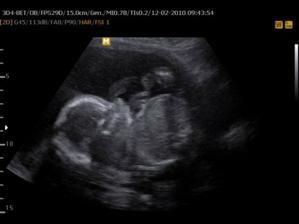

30.12. Jsem se byla zaregistrovat k porodu u Apolináře. ROK 2010 🙂 TO SE BUDOU DÍT VĚCI. 12.1. interní vyšetření + EKG a odběr - všechno OK, 14.1. UTZ žil kvůli natékání nohou (už ráno mám kotníky jako bambule). Výsledek: tromboza nehrozí UF!, nedomýkavost chlopní tepen, pže tělo je víc zatíženo. Doporučeno: nosit těhu punčochy, hodně pít, víc chodit, málo sedět a stát. Pak jsem utíkala na gyn na triplle testy a sestra mě objednala i na velký UTZ kam půjde i manža a budeme mimíska mít na DVD. Jsme oba natěšený! 20.1. UTZ ledvin - vše v pořádku. Tak velký UTZ proběhl OK. Nechceme vědět co to bude tak to stále nevíme 🙂)) . Triplletesty jsou taky v pořádku. 18.2. poradna - tak jsem měla nízký tlak 🙂)) jindy ho mám vysoký tak jsou trošku zmatený. Říkám, že mají blbý tlakoměr. Gynekologicky a miminkovsky všechno dobrý. 21.2. domluveno jméno pro klučíka - TOMÁŠEK .... ještě tu holčičku 😉)).